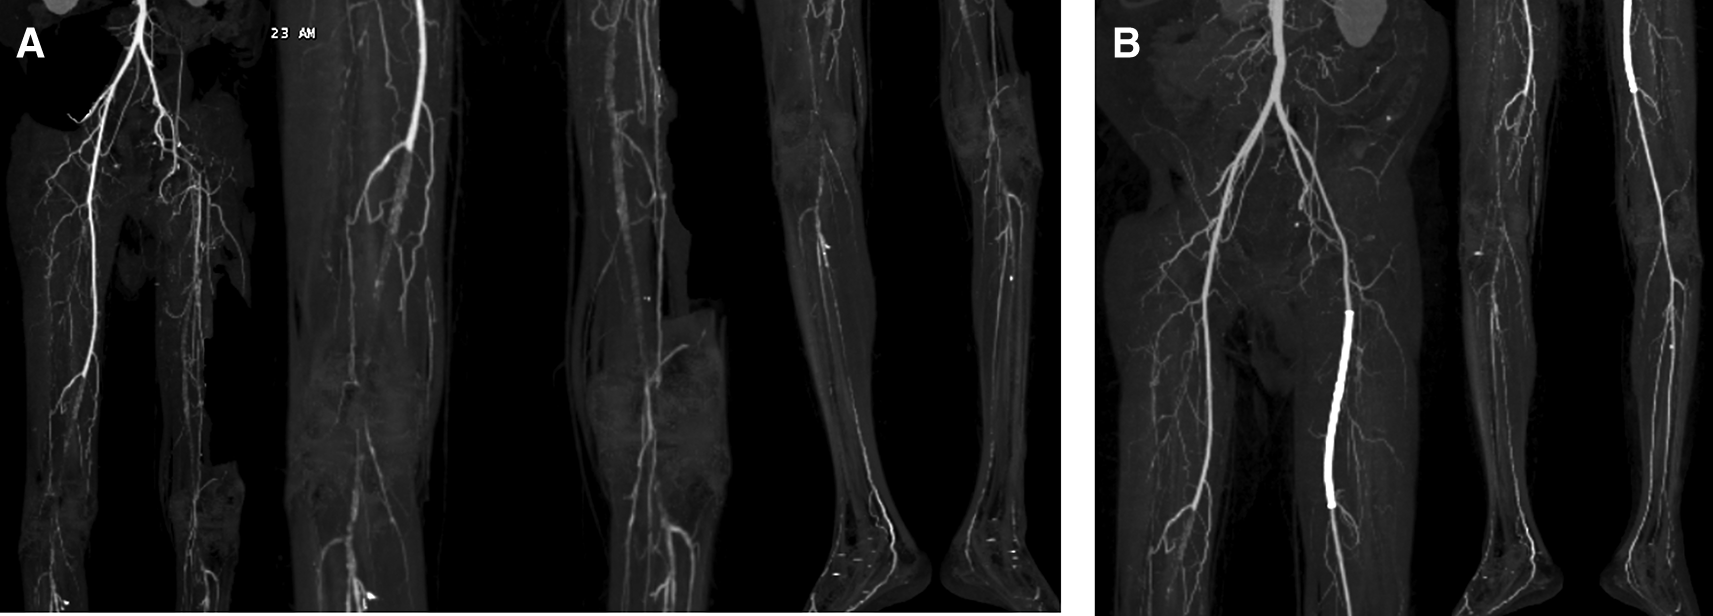

Vital signs were within normal limits. Physical examination revealed ulcer, hair loss, and atrophy on the left leg (Figure 5). Significant laboratory examination results were D-Dimer of 2990 ng/mL, total cholesterol of 233 g/dL, LDL of 187 g/dL, triglycerides of 164 g/dL, and urine albumin of 413 mg/L. His serum albumin was normal (184 g/dL). His right ABI was 0.5 on left was 0.33. Lower extremity DUS and CTA showed occlusion at level of left external iliac artery and 1/3 distal of right SFA with prominent plaque calcification (Figure 6A).

A. Pre-intervention, occlusion at level of left external iliac artery and 1/3 distal of right superficial femoral artery with prominent plaque calcification. B. Before 2nd intervention, positive flow until distal of the left leg with patent stent.

The patient’s diagnosis at the time was CLTI with ulcer on the left leg (Rutherford III-5, WIFi Score 1-3-0), chronic limb ischemia on the right leg (Rutherford I-3, WIFi Score 0-2-0), TASC II type D lession, and nephrotic syndrome. He was treated with heparinization and two episodes of percutaneous transluminal angioplasty (PTA). First, with POBA done at left Iliac Artery and SFA with addition of 6.0 × 120 mm drug-eluting stent (DES) overlapped with 6.0 × 80 mm (Boston Scientific, Marlborough, MA, USA) at SFA (Figure 7A). Second, POBA at mid–distal right SFA 5 months later (Figure 7B). CTA after the first procedure (Figure 6B) and angiography after second procedure with lower extremity DUS confirmed positive flow until distal vessel of both lower limbs. The patient was discharged without any complaint and received rivaroxaban, clopidogrel, aspirin, simvastatin, mycophenolic acid, and methylprednisolone as his routine medication. he was also educated to do exercise therapy.

A. First intervention, contrast flow until distal of left leg artery after percutaneous transluminal angioplasty. B. Second intervention, contrast flow until distal of right leg artery after percutaneous transluminal angioplasty.